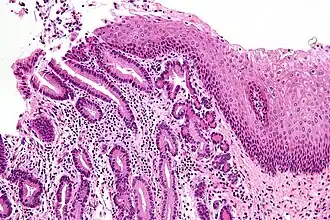

![]() Micrografía de la unión gastro-esofágica con metaplasia acinar pancreática teñida con hematoxilina-eosina. A la derecha, se observa la mucosa esofágica (epitelio escamoso estratificado). A la izquierda, se obseva la mucosa gástrica (epitelio cilíndrico simple). El epitelio metaplásico está en la unión (centro de la imagen) y tiene un citoplasma intensamente eosinófilo (rosa claro). | ||

En histología, se llama metaplasia a la transformación citológica de un epitelio maduro en otro que puede tener un parentesco próximo o remoto. Los fenómenos de metaplasia son completamente normales en los tejidos embrionarios que tienden naturalmente a diversificar, madurar y especializar sus células. También tienen lugar a partir de células madre totipotenciales o pluripotenciales, según se hable de tejidos embrionarios o adultos. En ciertas ocasiones la metaplasia implica una regresión en la especialización o maduración de las células hacia formas más primitivas para más tarde madurar hacia otra clase de células. La metaplasia puede presentarse como una respuesta adaptativa fisiológica frente al estrés celular y es reversible una vez cesa el estímulo agresor. No se considera una lesión neoplásica o premaligna. La metaplasia más común es la de epitelio columnar a epitelio escamoso.[1]